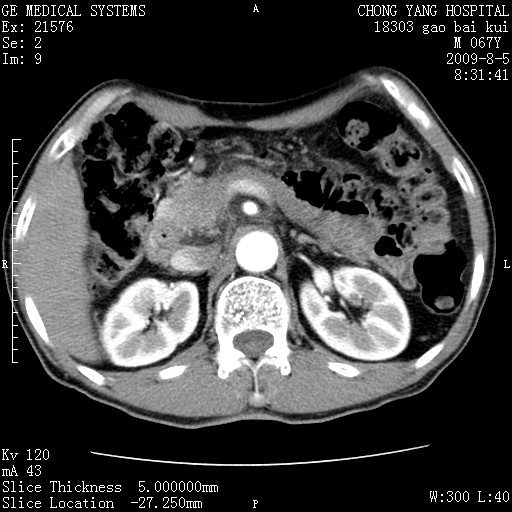

这个也过了,考虑胰腺钩突癌或壶腹癌,不除外胰管粘液乳头瘤伴胰管扩张,肝内胆管积气.

1)考虑胰头癌或壶腹癌并胰管扩张。2)肝外胆管扩张、积气,胆囊影未见;考虑术后改变。3)胃壁增厚?建议必要时行胃镜检查。

虑胰腺钩突癌或壶腹癌,不除外胰管粘液乳头瘤伴胰管扩张,肝内胆管积气.

考虑胰头癌并十二指肠受侵。